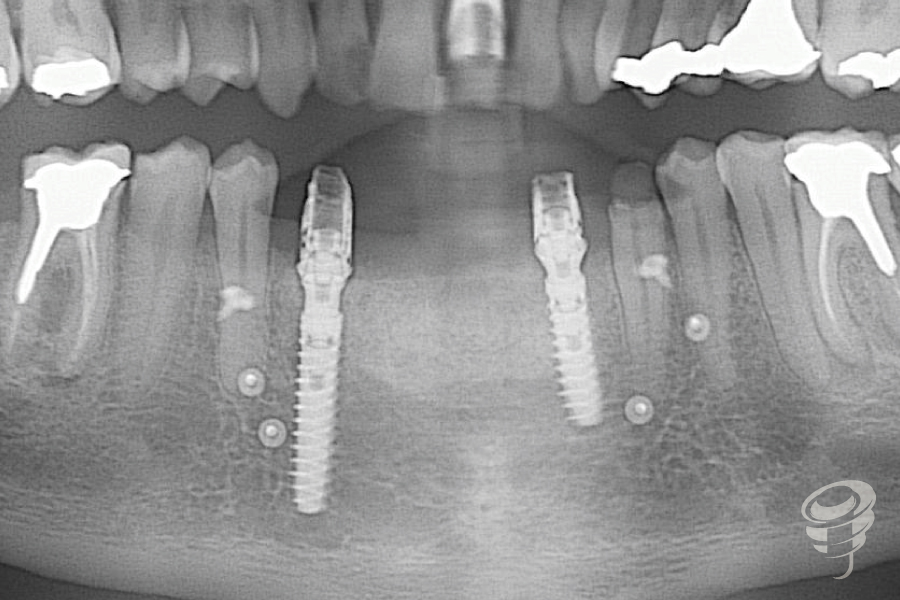

Una vez terminado el proceso de fresado y retirada la guía quirúrgica se colocan los Implantes Galimplant IPX de ø 3,5mm x Long. 14mm y ø 3,5mm x Long. 18 mm en posiciones de 32 y 43 postextracción previamente planificados. Dada la severa atrofia ósea horizontal el implante en posición de 32 queda fenestrado. Se realiza una regeneración ósea horizontal con xenoinjerto y membrana de colágeno.

Colocación de los pilares Multiposición recto estéticos y sus pilares de carga inmediata

Regeneración ósea horizontal con xenoinjerto y membrana de colágeno. Colocación de pilares multiposición recto estetico